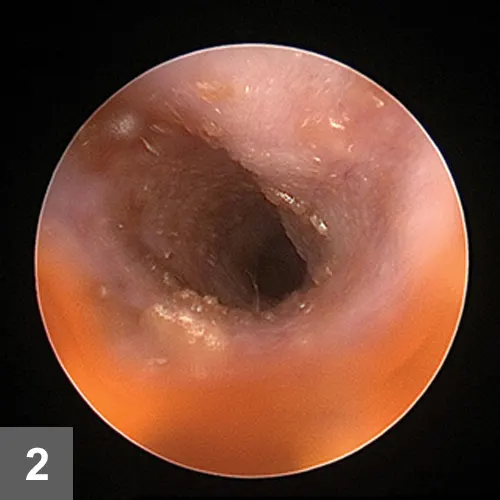

Figure 2. At the first recheck (2 weeks after initiation of treatment), the dog’s ear was erythematous with mild hyperplasia and ceruminous exudates. The breed-related narrowness of the ear canal in addition to discomfort precluded a complete view of the tympanic membrane without anesthesia.

The ears were normal on palpation. Stenosis of the horizontal canal was mild for the breed with mild hyperplasia. Yellow-brown ceruminous exudate and medication were present, preventing  complete visualization of the tympanic membranes (Figure 2).